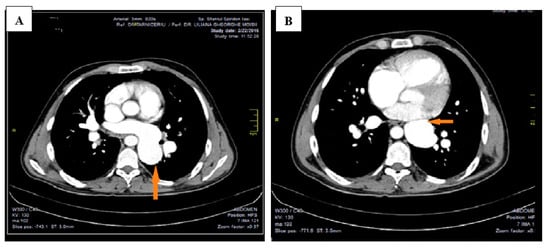

This led to further investigations and a thoracic CAT scan was performed. The thoracic CAT scan showed a vertical collecting canal (vein) located in the left side of the mediastinum that was considered to be a persistent left superior vena cava associated with an anatomical variation of the pulmonary venous return (Figure 1A,B). Upon detailed exploration and reconstruction, images revealed that the pulmonary venous drainage takes place above the heart, and all four pulmonary veins are ending into a common collecting canal and then this trunk opens into the left brachiocephalic vein that drains into the superior vena cava (Figure 2). It was not noted a connection (opening) between the collecting canal and the left atrium. Upon a closer investigation and interpretation of the thoracic CAT scan images, the patient was seen to have an atrial septal defect, and therefore oxygen rich blood was sparse due to a right-to-left shunt and drains blood into the left atrium (Figure 3).

Figure 1. Thoracic CAT scan: (A)—a vertical collecting canal located in the left side of the mediastinum that opens into the left brachiocephalic vein. Arrow shows the presence of a vertical collecting canal.; (B)—not noted connection (opening) between the collecting canal and the left atrium. Arrow shows the relation of a vertical collecting canal with left atrium.